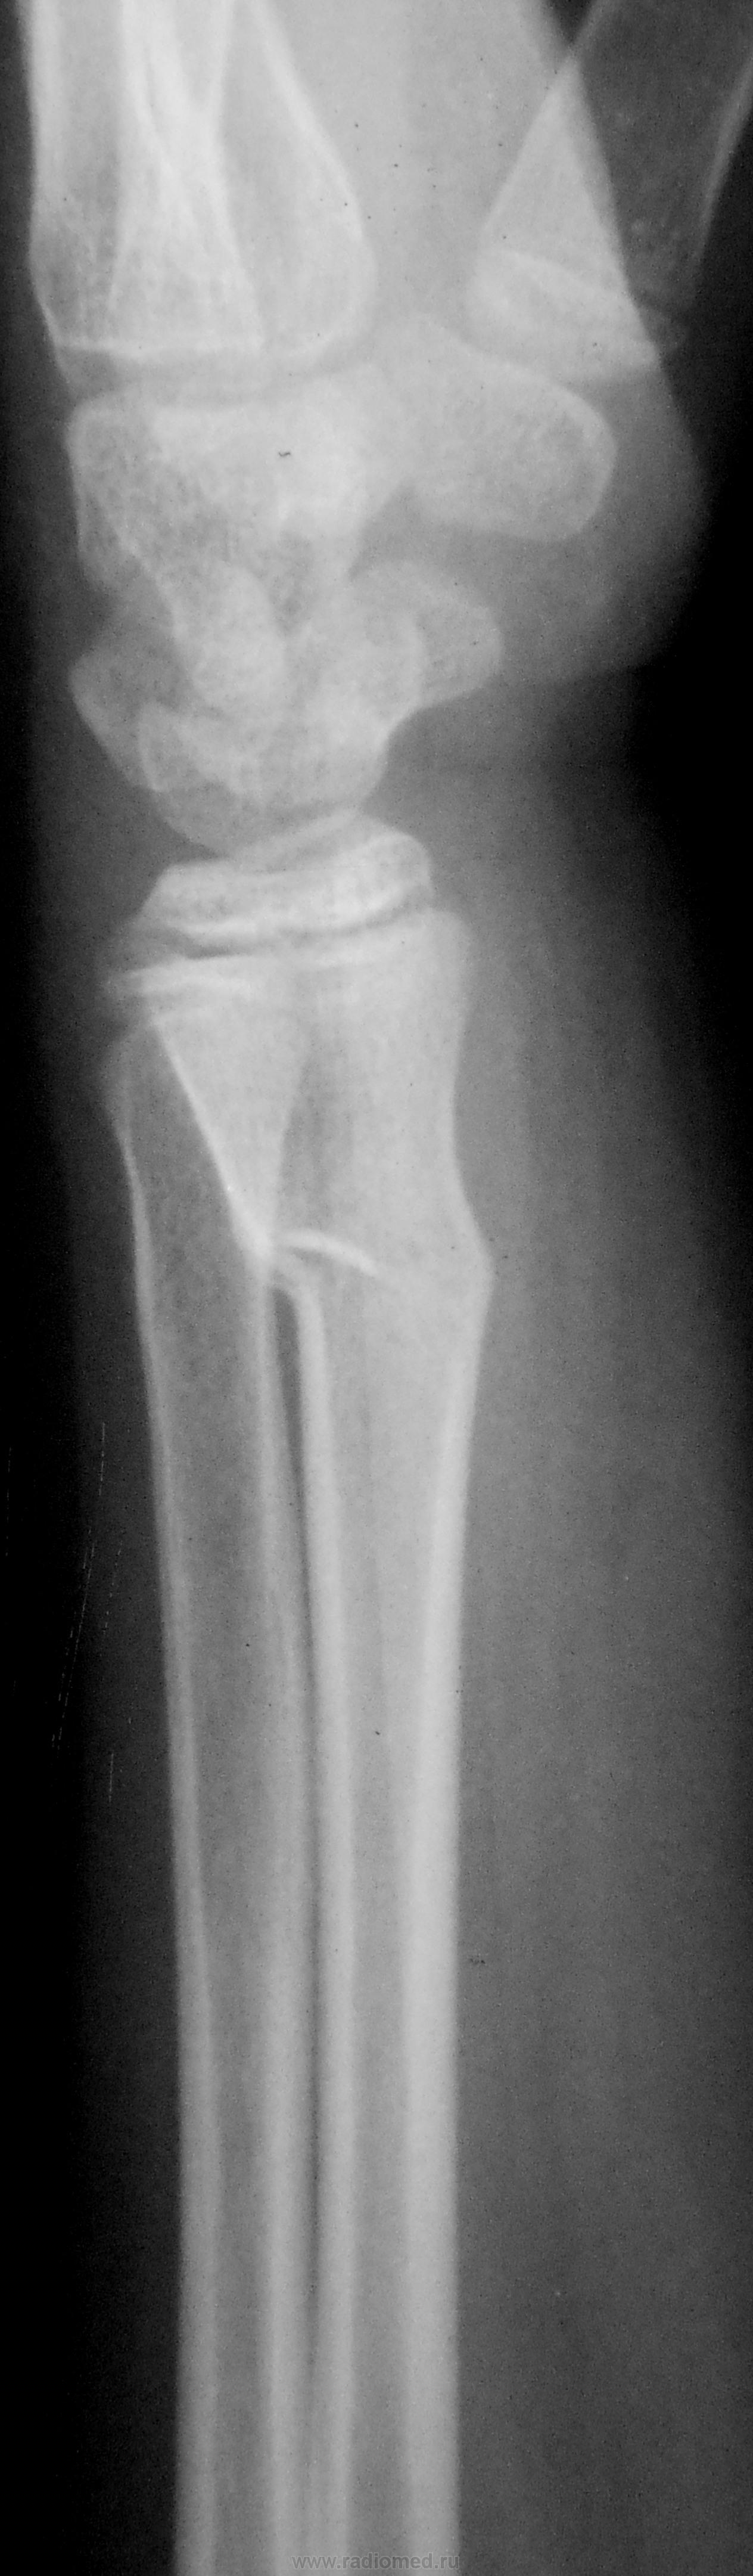

Пол пациента: Женский пол Тип патологии: Травма Область исследования: Скелетно-мышечная система Методы исследования: Rg Классика. https://radiomed.ru/sites/default/files/styles/case_slider_image/public/user/12/2.dscn0057a.jpg?itok=dZ2pZ746 ID:23193 Tue, 18/09/2012 - 17:42 #1 Соломин Виталий... Offline Last seen: 6 years 4 months ago Joined: 04.04.2012 - 21:47 Posts: 1096 "Зеленая веточка" в типичном месте. Лучше подправить. Tue, 02/10/2012 - 20:54 #2 Катенёв Валенти... Offline Last seen: 7 years 5 months ago Joined: 22.03.2008 - 22:15 Posts: 54876 Снят гипс.Приложения:

"Зеленая веточка" в типичном месте. Лучше подправить.